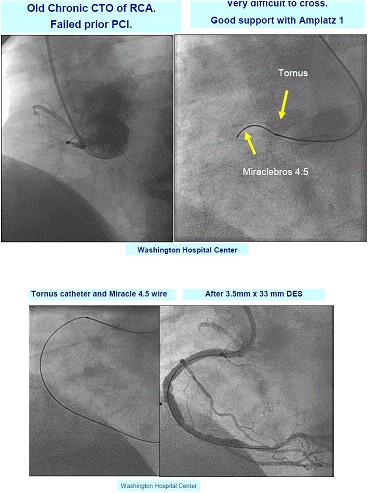

附华盛顿医学中心病例:见图1,右冠状动脉CTO病变,导丝不能通过,换用Amplatz指引导管,在Tornus导管辅助下,Miracle 4.5导丝通过闭塞段,并成功置入一3.5mm /33mm药物洗脱支架。

图1